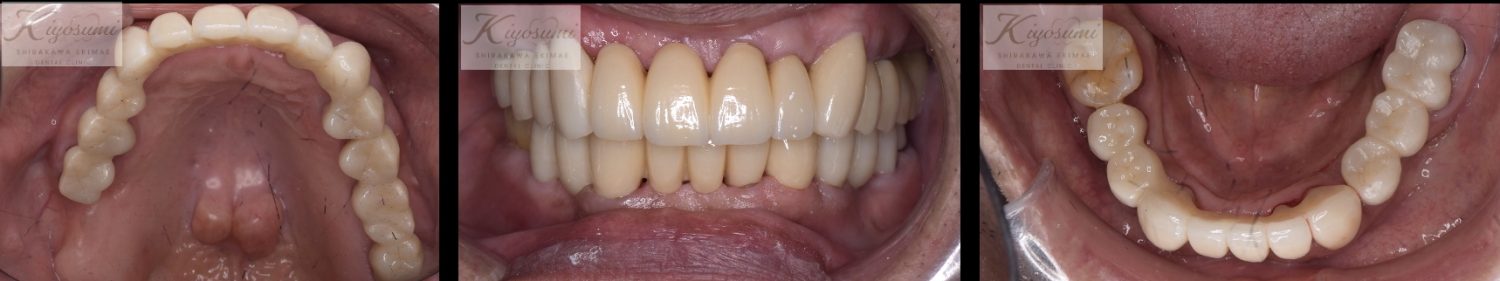

| 主訴 | 歯が揺れて噛めないので、噛めるようにして欲しい。 |

| 治療内容 | 基本的な歯周病治療、根の治療を実施し、歯の高さが足りない箇所は歯冠長延長術、保存が難しい歯は一部歯根分割抜去を行いました。欠損部はインプラントを用いず、ジルコニアブリッジで仕上げています。 |

| 想定されたリスク | ※残存している歯の本数が少ないため、残っている歯だけでブリッジを行うには長期予後が見込めない可能性があり、患者さんにご理解をいただいたうえで被せ物を行っています。 ※歯周病治療や根の治療をしても歯を残せない可能性がありました。 |